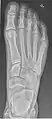

- Foot / Toes - Dorsoplantar, Oblique and Lateral.[19]

Normal right foot by dorsoplantar projection

Oblique projection

Lateral projection